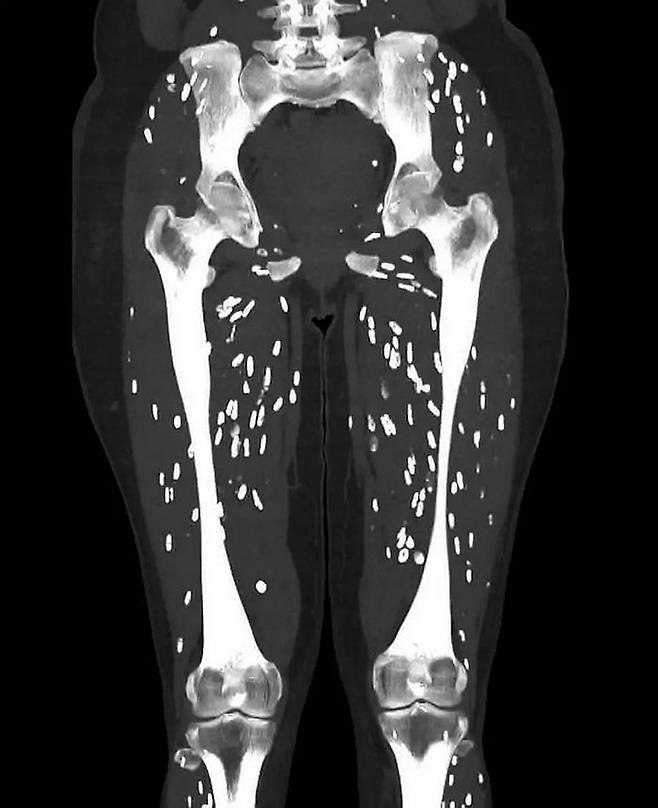

[헤럴드경제= 박영훈 기자] 유독 삼겹살을 좋아하는 한국인들이 관심있게 봐야 할 충격적인 사진이 나왔다. 덜 익인 돼지고기를 먹고 기생충에 감염된 환자의 CT 사진이 공개됐다.

미국 플로리다 대학교 샘 갈리 박사는 최근 엑스(X·옛 트위터)에 사진 한 장을 게재했다. 갈리 박사는 해당 사진이 ‘낭미충증’이라는 기생충에 감염된 환자의 것이라고 밝혔다.

낭미충증은 주로 덜 익은 돼지고기 등을 섭취해 감염된다. 유충이 장을 빠져나와 신체 다른 곳의 조직과 기관으로 이동하면 낭종이 생기는데, 갈리 박사가 공개한 환자의 사진은 다리로 옮겨진 낭종의 모습을 선명하게 담고 있다.

대퇴골을 시작으로 무릎 관절 아래까지 유충을 담고 있는 수많은 낭종이 퍼져 있는 것을 볼 수 있다.

체내에 서식하게 된 유충은 딱딱한 덩어리처럼 느껴질 수 있는 석회화된 낭종을 형성하는데, CT 스캔을 하면 마치 흰색 타원형의 쌀알처럼 보인다.